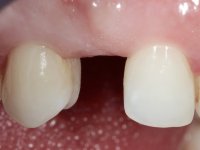

The patient wanted to "replace a milk tooth that fell” and would like a fixed tooth, but did not want to extract the impacted tooth, nor to place an implant.

Female patient, 43 years old, non-smoker. Showed an edentulous space in the upper right canine area, resulting from tooth 1.3 impaction. The space had a mesio-distal diameter reduced to the normal size of the upper canine. This is consistent with the presence in the arch of the deciduous canine up to two years ago). Orthopantomography allows clearly view of tooth 1.3 impaction.The patient has a thick gingival phenotype and tolerable oral hygiene.

To define the dental zone to be covered by the Maryland bridge retainers, the patient was asked to perform maximum intercuspidation movements, and the contact points were marked with articular paper. Tooth preparation of the interproximal surfaces was made, to create a prosthetic insertion axis. It was sought that the mesio-distal diameter at the incisal level was equal to the diameter mesio-distal at the cervical level, that is to say, the interproximal walls were parallelized. Tooth preparation was done with fine grain diamond drills, and later polishing was done with abrasive discs. Color information was collected even before confection of the impression, to avoid dehydration of the arcade. Definitive impression was made using wash technique impression with silicone of heavy and regular consistency, both with fast setting, and a working plaster model was prepared in the lab. A laboratory scanner was used to scan the working model, and later, the infrastructure for the Maryland bridge was made using a CAD-CAM process. Ceramic was placed on this subframe. A ceramic adhesive was applied to the internal surface of the wings and connectors, which would enable bonding to the adjacent teeth. The adhesive bridge was bonded in the mouth following the conventional bonding technique. After bonding, the protrusion and laterality movements were carefully checked to avoid undesirable contacts.